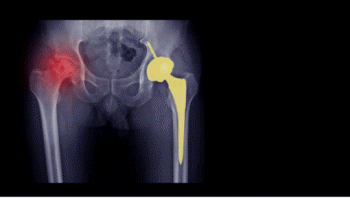

골괴사는 뼈에 공급되는 혈액이 차단되어 뼈 조직이 점점 죽어가는 질환입니다. 주로 대퇴골두(허벅지 뼈 머리 부위), 팔 위쪽, 어깨, 무릎 등에서 발생하며, 모든 연령층에서 발병할 수 있습니다.

- X-ray(방사선사진) : 후반부 이상 감지

- 관절 치환술(인공관절) : 손상 부위가 넓을 때 주로 시행